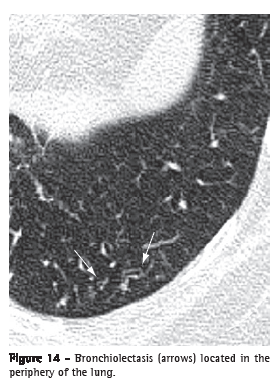

Bronchiolectasis (bronquiolectasia)

Bronchiolectasis refers to the dilatation of a bronchiole. It is analogous to bronchiectasis, but it affects an airway of much smaller diameter, identified in the periphery of the lung (Figure 14). Bronchiolectasis manifests as rounded or tubular structures, generally located in the periphery of the lung, with thick walls or filled with secretion (see also Tree-in-bud pattern).(3,7) It can also be combined with other pulmonary opacities and to the distortion of the parenchyma in cases of fibrosis.

See also Traction bronchiectasis and traction bronchiolectasis.